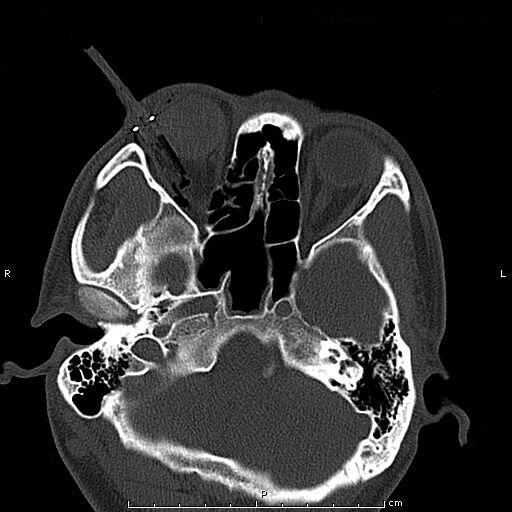

患者青年男性,因“右眼被鋼筆戳傷2小時余”入院,眼科查體:視力:右無光感,左0.4。眼壓:右不能檢查,左正常。右眼上瞼紅腫,鋼筆自顳上方眼瞼刺入,末端位置不詳,睜眼困難;結膜充血、水腫,角膜尚清,前房積血,余眼內結構窺不入。左眼未見明顯異常。入院后完善眼眶CT檢查,印象:右眼眶異物并右眼球破裂傷、眶內壁骨折,異物嵌頓于眶壁。鋼筆內含墨水,傷情重且復雜。

經科室討論、充分評估患者病情,與患者進行病情溝通后,擬于全麻下實施右眼眶壁異物取出+眼球破裂傷清創縫合探查+眼瞼皮膚裂傷清創縫合+萬古霉素玻璃體腔注藥術。由于鋼筆筆尖與筆筒游離且筆尖彎曲倒鉤于眶壁,使異物取出難度大大增加,經專家團隊討論,決定在鼻內窺鏡協助下聯合眶內入路分離、截斷內直肌、下直肌成功將眶內壁異物自鼻腔完整取出,手術取得圓滿成功。